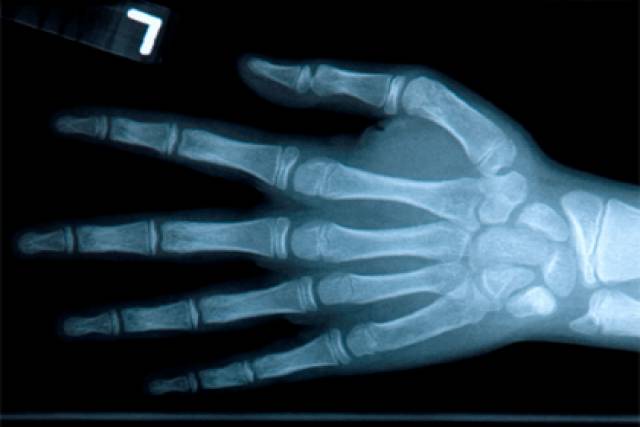

Для подтверждения наличия диагноза проводится рентгеновское обследование, в ходе которого определяется степень изменения сустава и контролируется его состояние на предмет наличия воспалительного процесса.

Рентген кисти руки

- С помощью рентгена. На снимке будет видна степень деформации соединения: уменьшение щели соединения, остеофиты, различные образования.